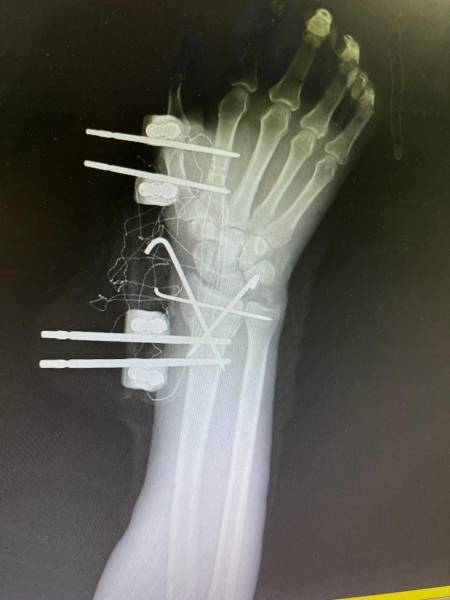

- إجراء عمليات جراحية معقدة و دقيقة في مجال العظام و المفاصل و الكسور و الإصابات ، رغم الضغط الكبير على المستشفى و أعداد المراجعين الكبيرة.

- تطبيق تقنيات جراحية حديثة و متقدمة، و ذلك في ظل التحديات التي يواجهها الفريق بسبب أعداد المرضى و المراجعين الكبيرة.